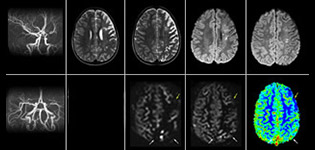

Le marquage des spins artériels pseudo-continu (pCASL) a été développé pour l’imagerie de perfusion cérébrale sans agent de contraste. “C’est vraiment intéressant pour les patients en pédiatrie, où la tendance générale est de limiter l’administration de produits de contraste”, explique le Dr Miller. Accroître la confiance dans des applications spécifiques “Nous avons renforcé notre confiance à l’égard du pCASL en le comparant à l’imagerie de perfusion de contraste. Une fois que nous étions sûrs qu’il représentait ce que les perfusions de contraste représentaient, nous avons amélioré la fiabilité de nos diagnostics par l’imagerie en série de la phase aiguë ou des phases à long terme chez plusieurs patients atteints d’anomalies artérielles.

Le Dr Miller utilise le pCASL pour tous les patients qui se présentent avec des anomalies cérébrovasculaires telles qu’un AVC aigu, ainsi que les patients présentant des signes d’inflammation cérébrale grave, et occasionnellement les patients atteints de tumeurs pour évaluer l’état de perfusion de leurs tumeurs.

“En association avec l’imagerie de diffusion pondérée, il aide à évaluer plus en détail le degré d’anomalie de perfusion chez un patient souffrant d’une ischémie aiguë. Plusieurs de nos patients souffrent d’insuffisance artérielle chronique à cause d’anciennes anomalies artérielles ou d’anomalies artérielles acquises telles que la drépanocytose ou la neurofibromatose. Parfois, la première manifestation de la progression de la maladie chez l’enfant est une réduction dans la perfusion cérébrale avant que les symptômes de l’AVC ne se manifestent cliniquement ou une réduction dans l’imagerie de diffusion pondérée. Nous utilisons le pCASL pour aider à définir l’anomalie de perfusion.”

Je recommanderais également aux autres nouveaux utilisateurs de commencer à interpréter les images pCASL par rapport aux autres images standard, T2, FLAIR et DWI, jusqu’à ce qu’ils puissent interpréter ces images par eux-mêmes en toute confiance.” “L’utilisation du pCASL est efficace chez les patients présentant une sténose cérébrovasculaire chronique, pour laquelle les cliniciens ont besoin d’informations sur la façon dont les mécanismes compensatoires du cerveau fonctionnent pour permettre la perfusion cérébrale. Souvent, les cliniciens prennent en compte la façon dont les mécanismes compensatoires apparaissent pour pouvoir administrer la perfusion adéquate au cerveau du patient. Ils peuvent également intervenir chirurgicalement ou prendre d’autres décisions de prise en charge.” “Une autre application spéciale est l’évaluation de la réactivité cérébrovasculaire avec un examen de perfusion Diamox, lors duquel on soustrait deux ensembles d’images pCASL.”

“Pour nous, désormais, le pCASL est plutôt devenu une acquisition de première ligne pour évaluer la perfusion, par opposition à l’imagerie de perfusion basée sur la DSC avec agent de contraste. Chez les patients qui ne sont pas censés recevoir de produit de contraste, nous pouvons réaliser un pCASL pour l’imagerie de perfusion sans avoir à arrêter l’examen, sortir le patient et poser une IV. Il annule également la nécessité du post-traitement pour les contrastes de susceptibilité dynamiques. En outre, il nous permet de répéter l’imagerie de perfusion sur le même patient et pendant la même imagerie, ce qui nous aide en termes de mouvements du patient, ou lorsqu’une acquisition doit être effectuée avant l’imagerie de perfusion pharmacologique.”